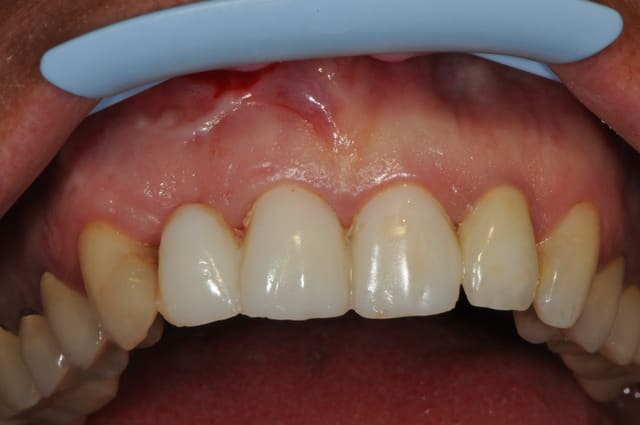

voici - voilà:

photo

1: j+ 2 ou 3 jours

2: j+8 mois

3-4-5: j+ 2 ans

sur la photo 3 on voit à la gencive que l'aspect est moins granité au niveau du col.

c'était ça l'indice pour trouver Charlie.